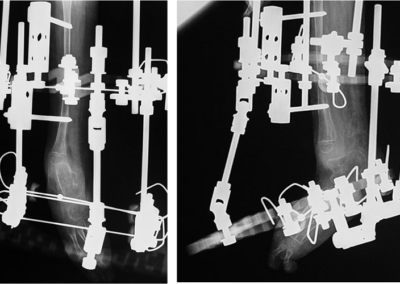

Congenital Pediatric Orthopedic DiseasesDec 30, 2021 | Case ExamplesBilateral GKD Case 1 Bilateral GKD Case 2 Bilateral GKD Case 3 Bilateral GKD Case 4 Congenital Clubfoot Fibuler Hemimeli Tibial Hemimeli PFFD